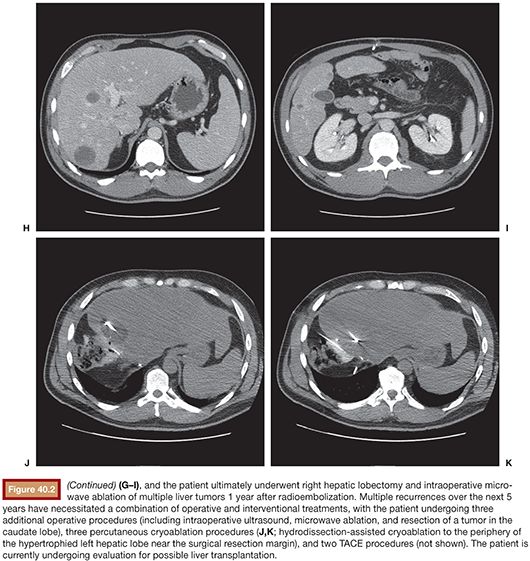

From radiologykey.com

Neuroendocrine Tumors Radiology Key Neuroendocrine Cancer Esmo Authorship includes a multidisciplinary group of experts from different institutions and countries in europe. Predictive and prognostic factors for treatment and survival in 305 patients with advanced gastrointestinal neuroendocrine carcinoma (who g3): In order to identify neuroendocrine tumours, a synaptophysin and/or insm1 staining must be carried out in tumours with a solid, trabecular, gyriform or regular glandular growth pattern, uniform. Neuroendocrine Cancer Esmo.